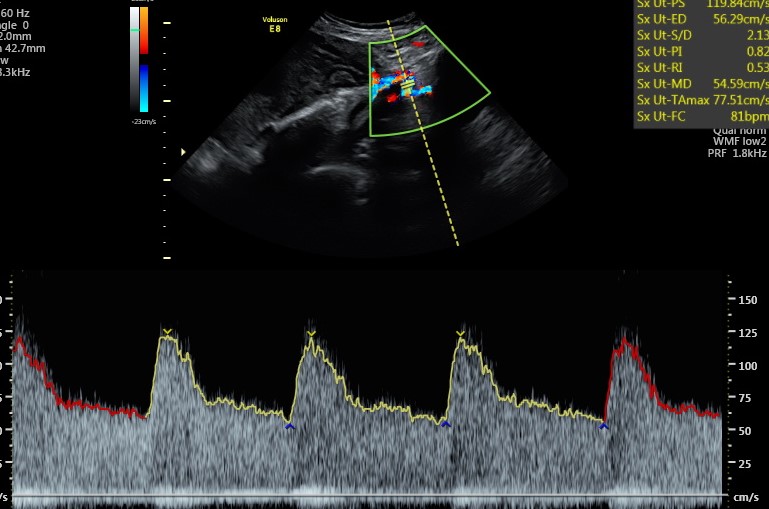

A livello ecografico non ci sono particolari controlli da fare, se non quello della arterie uterine se all’ecografia morfologica erano ancora un po’ vasocostrette.

Infatti la placenta in questo mese e mese e mezzo ha continuato la sua opera di modificazione delle arterie uterine per renderle dei vasi a bassa resistenza e conseguentemente assicurandosi un buon apporto di sangue per il resto della gravidanza. Se anche in questa occasione le arterie uterine dovessero ancora avere le resistenze aumentate è importante pianificare una ecografia di accrescimento ogni mese e monitorare la pressione della mamma su base quotidiana.